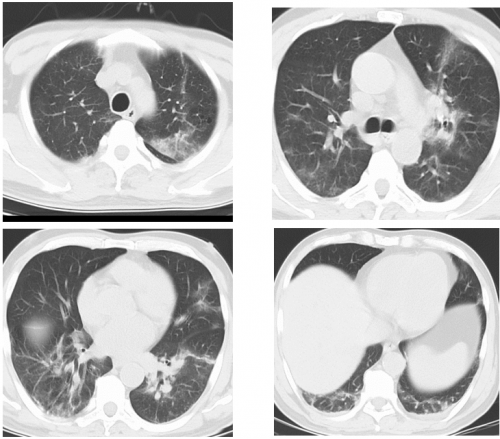

胸部CT:双肺炎症,双肺大面积片状淡磨玻璃影

2025-11-04 CT检查结果:双肺间质性炎性改变,双肺散在纤维条索及慢性炎症。局限性肺气肿。左肺上叶结节。

肺CT(长春中医药大学附属医院,2025-11-30):

1、双肺问质性炎性改变,与2025-11-4日前片比较 右肺中叶病变新增,余双肺病变密度减淡、范围减小,请结合临床病史、随诊复查。

2、双肺散在纤维条索及慢性炎症。

3、局限性肺气肿。

4、左肺上叶结节,定期复查。